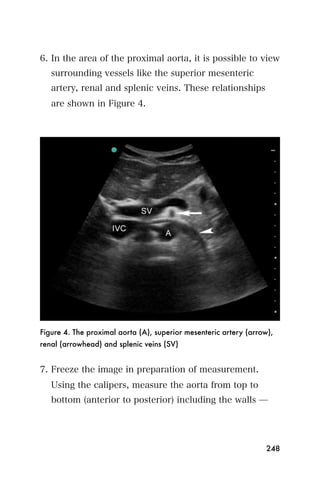

gallbladder wall thickening, portal edema, and

lymphadenopathy can also be seen.

Figure 18. Acute hepatitis (a, b and c). Diffusely increased

heterogeneity and echogenicity of hepatic echotexture consistent with

diffuse inflammatory process from hepatitis.

170

Cirrhosis & portal hypertension

In cirrhosis, the liver will demonstrate both parenchy-